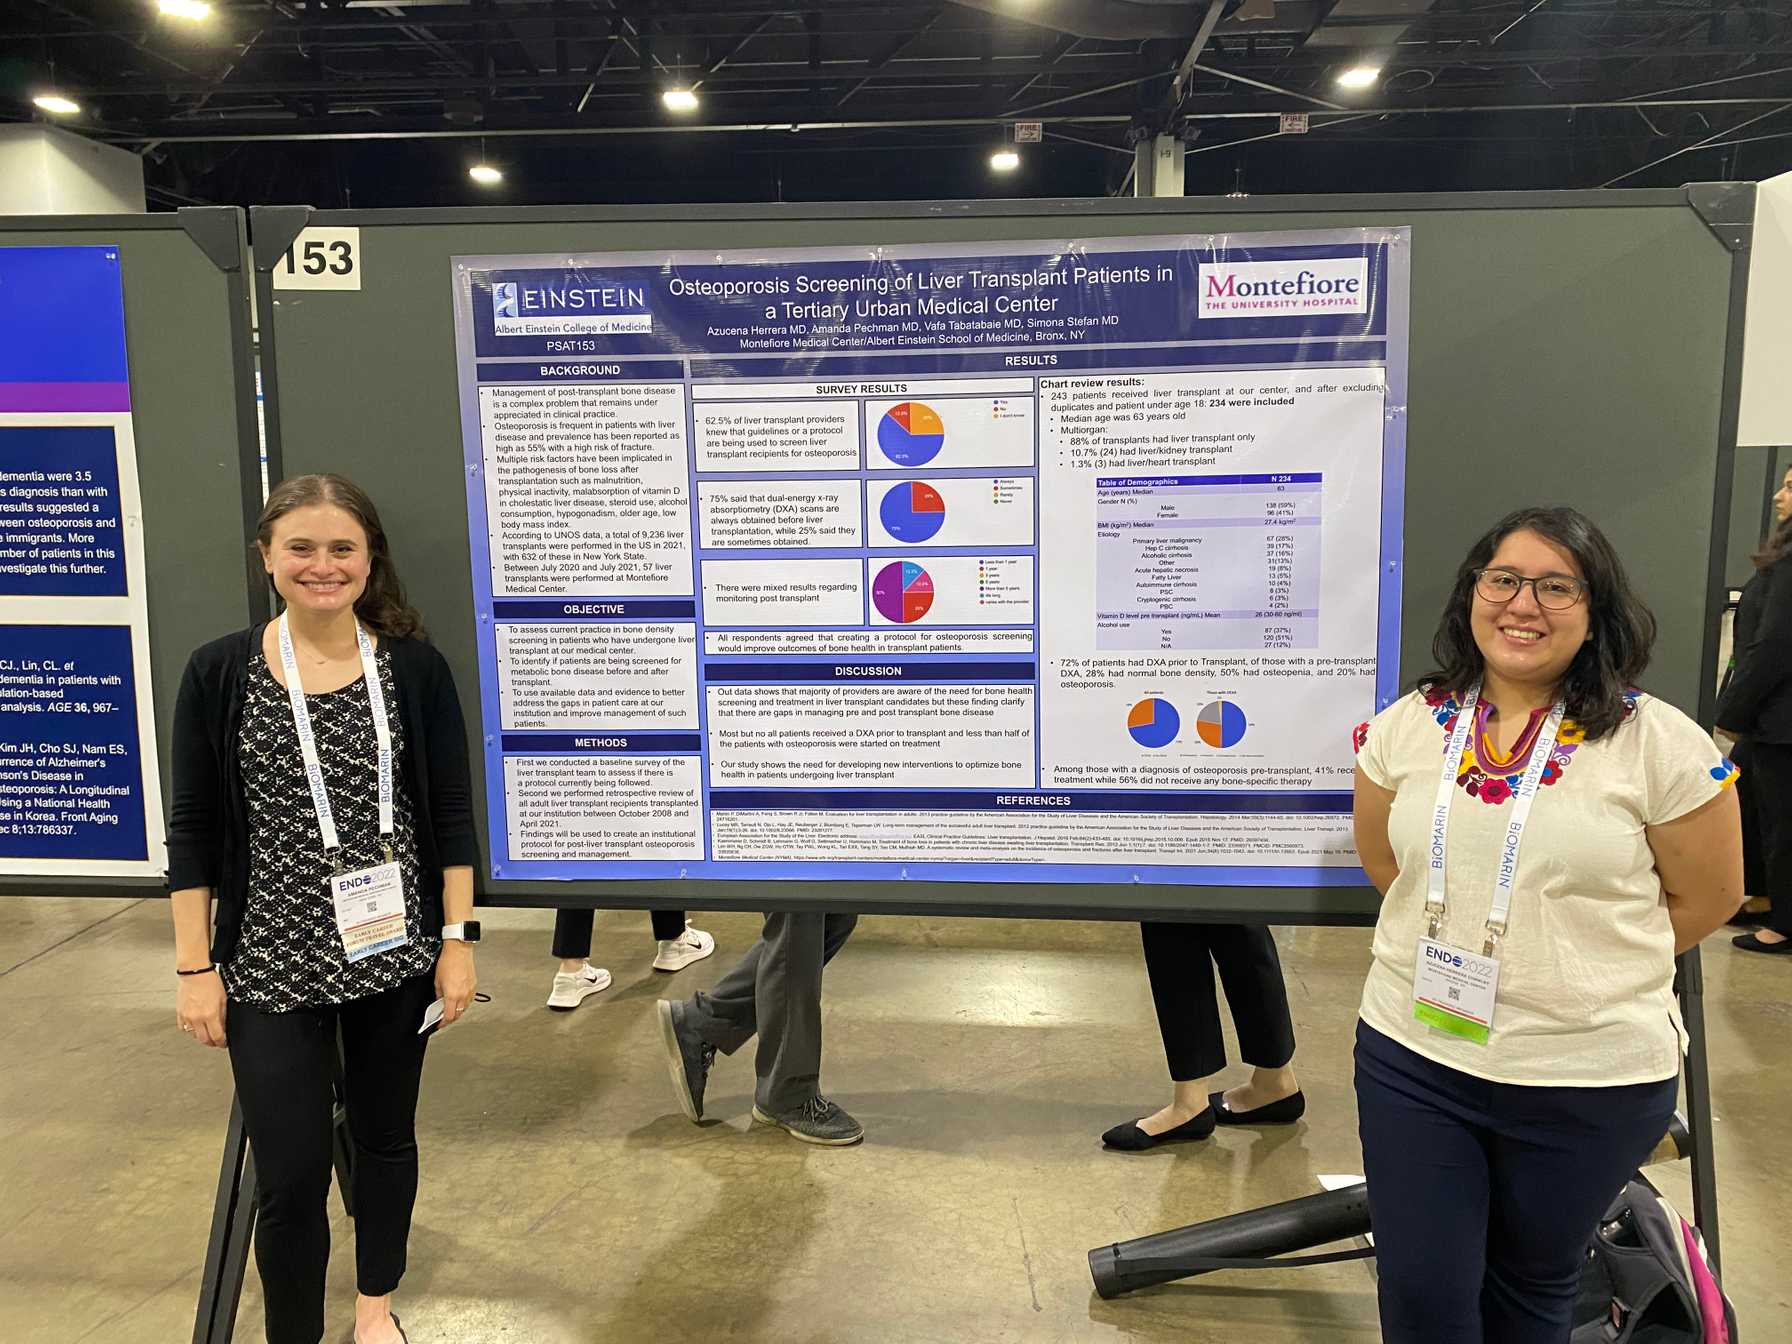

- Contribution to medical literature through the preparation of case reports, abstracts, posters and manuscripts to present in local, regional and national conferences and forums

Offering rich opportunities for research

Researchers from Albert Einstein College of Medicine secured $178 million from the National Institutes of Health (NIH) in 2019, with $14.7 million in funding granted to researchers in the Division of Endocrinology, Diabetes and Metabolism. The Division carries out ongoing clinical, basic science, translational and behavioral research in a range of endocrine science areas, including diabetes and aging research, along with emerging opportunities in thyroid, metabolic bone disease and neuroendocrine research.

Our NIH-funded research centers include the Einstein Sinai Diabetes Research Center, home to more than 120 faculty laboratories conducting basic, translational and clinical research in diabetes, obesity and metabolism; the New York Regional Center for Diabetes Translation Research, specializing in bio-psychosocial and behavioral research, with a focus on the social determinants of health; the Institute for Aging Research and Nathan Shock Center of Excellence in the Basic Biology of Aging, which conducts basic, translational and clinical research; and the Global Diabetes Institute, which establishes strategic global partnerships for research on lean diabetes and improving diabetes education.

Endocrinology Fellows become familiar with research in their first year under the stewardship of Sofiya Milman, MD, Associate Program Director for Research. Depending on their experience and future career interests, fellows can choose to initiate their own research project or join an ongoing project, working with helpful and experienced mentors. Fellows also participate in didactic seminars on research methodology, scientific writing and quality improvement studies. During their training, fellows gain valuable research experience, and most contribute to their field by presenting their findings at regional or national conferences or in a manuscript.